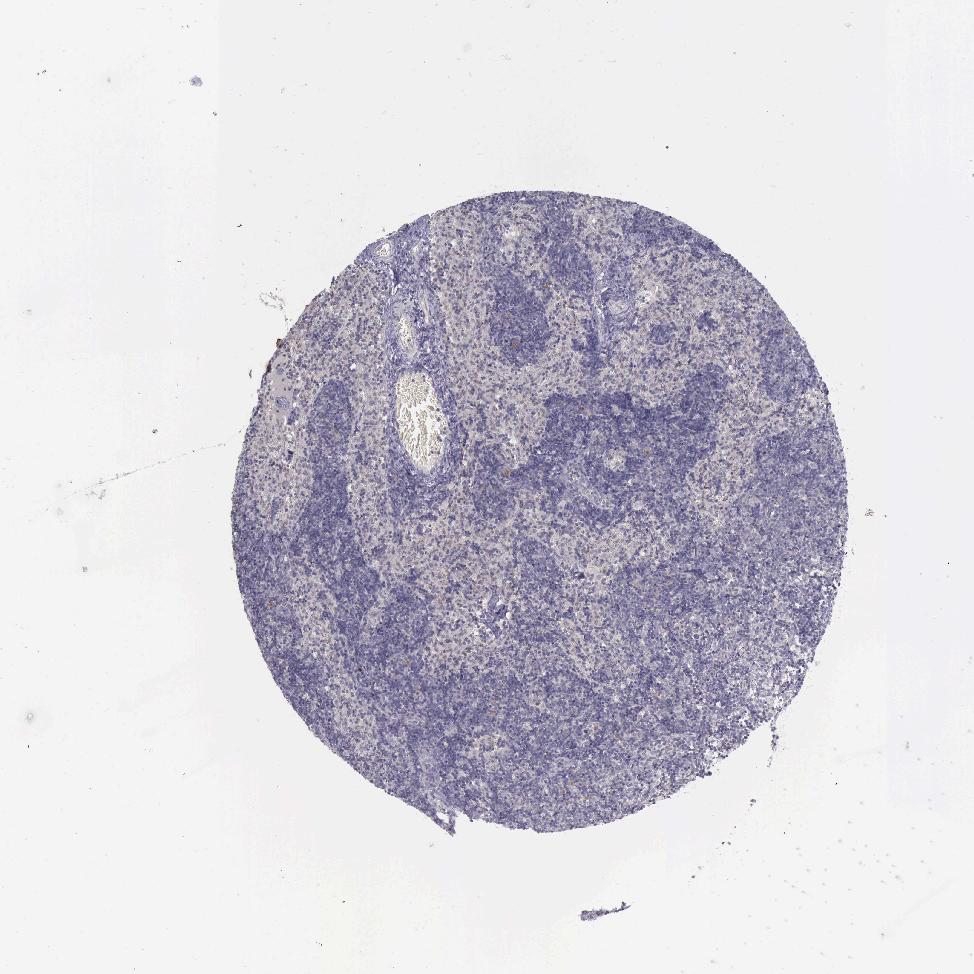

TISSUE PRIMARY DATA LYMPH NODE Show tissue menu

Lymph node

LYMPH NODE - Expression summary

LYMPH NODE - Antibody stainingi

Antibody staining in the annotated cell types in the current human tissue is reported as not detected, low, medium, or high, based on conventional immunohistochemistry profiling in selected tissues. This score is based on the combination of the staining intensity and fraction of stained cells.

Each image is clickable and will lead to virtual microscopy that enables deeper exploration of all samples and also displays staining intensity scores, fraction scores and subcellular localization as well as patient and tissue information for each sample.

Antibody HPA001056Antibody CAB005081

Germinal center cells Not detectedLow

Non-germinal center cells Not detectedNot detected